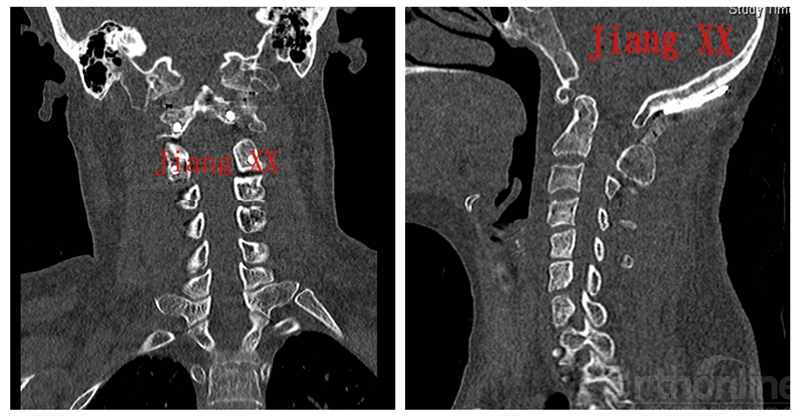

术后CT

术后一年CT

一例患者因C1先天性发育不良与枕骨融合,故采用枕颈固定。随访时间>12个月,骨性愈合100%,关节突关节之间无塌陷。术后神经功能明显改善,其余3例行单纯寰枢椎固定。

下颈椎原来代偿性改变的曲度,无论是过曲还是过伸都得到有效恢复,颈椎的矢状面力线更加平衡。